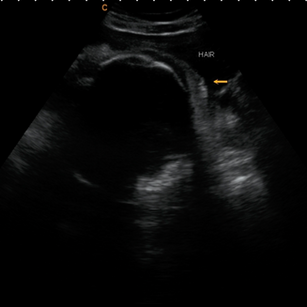

32 Weeks Pregnant

At 32 weeks pregnant, your baby is well into the third trimester and making big strides in growth and maturity. They’re starting to look more like a full-term newborn, but still need more time for their brain, lungs, and fat stores to fully develop.

Movements

Space in the womb is getting tighter, but your baby is still very active. You’ll notice more rolling, stretching, and shifting than sharp kicks.

Vernix & Lanugo

Vernix caseosa (the creamy coating) continues to thicken, protecting baby’s skin.

Lanugo (fine body hair) is starting to shed, though some may remain at birth.